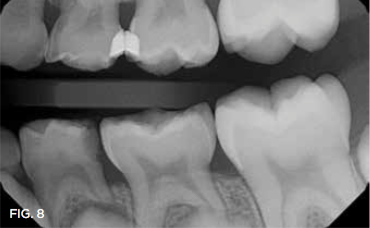

Case 3. This 10-year-old boy was brought to the office for a second opinion regarding restoration of the left primary first molar, which was causing sensitivity (Figure 8). The boy's mother reported that a "tooth-colored filling" had been suggested at another office. The boy was terrified of needle injections and, according to his mother, had required sedation in prior years for restoration of maxillary primary molars. SDF was applied (Figure 9), tooth sensitivity was eliminated, and in 3 months, clinical evaluation and a periapical radiograph confirmed that no other treatment would be needed until the tooth exfoliated (Figure 10 and Figure 11).

Fig 8. 10-year-old patient with distal caries lesion of primary  rst molar. (

Fig 8

Fig 11. 3 months after SDF application, no additional treatment needed.

Fig 11